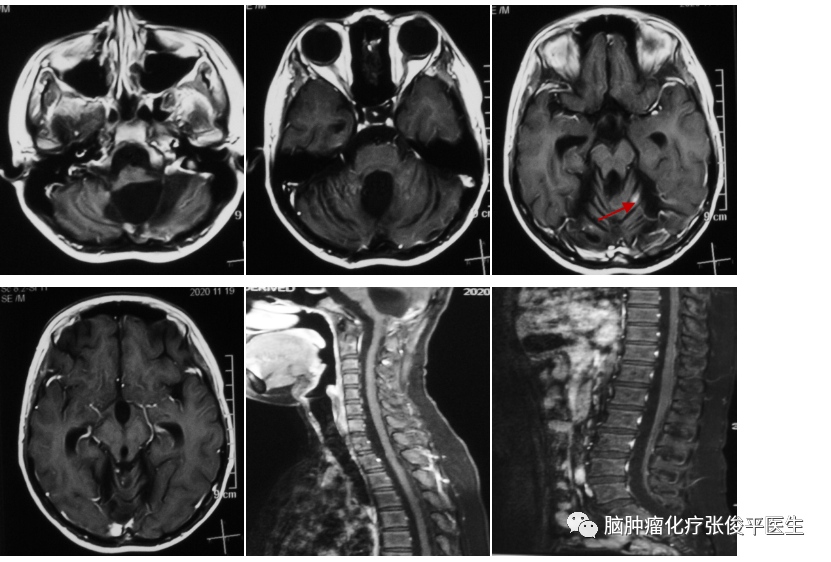

患者董**,男,14岁。2019年年初患者出现恶心呕吐,未重视。2019年4月患者出现头痛,遂行头部MRI示:双侧小脑半球、蚓部、四叠体区占位。患者于2019-4-16接受手术治疗,手术顺利,术后病理提示髓母细胞瘤,WHOⅣ级。分子分型示:偏向Group4型。患者颅内及脊髓伴有播散病灶,且术后出现缄默,遂行4周期ICE方案化疗,化疗后复查核磁提示颅内、髓内病灶缩小、减少。2019年8月接受了全中枢放疗,放疗后继续化疗4周期,末次化疗时间:2020-2-26。2020-3-17复查头颅及全脊髓核磁提示病灶基本消失。停止治疗,定期随访核磁。2020-7-2复查核磁提示肿瘤复发,颅内、全脊髓多发异常强化影如(见下图)。

结合患者病史,化疗结束后4月余即出现肿瘤复发,肿瘤进展快,给予更换方案化疗,具体用药为:替莫唑胺+依托泊苷+阿帕替尼。化疗2周期后,2020-9-17复查头颅及全脊髓核磁提示颅内病灶明显减少,疗效评价:PR。患者目前仍在化疗中,2020-11-18复查核磁提示仅余左侧小脑半球小点状强化影(见下图)。